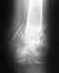

произошла травма коленного сустава: нога подвернулась и затем подогнулась, но падения на колено небыло(поставили диагноз: надрыв крестообразной связки) . было кровоизлияние в суставе, откачивали 4 раза в течение недели после травмы( в это время находился в ортезе), затем еще через неделю прошел курс ультрозвука с гелем траумель и параллельно гарячий воск с озокеритом.через 2 недели после травмы начал почуть чуть наступать на ногу(в ортезе) с костылями. через 3 недели после травмы начал ходить с одним костылем(но в жестком наколеннике из неопрена) и разрабатывать ногу. сейчас уже пятая неделя после травмы хожу без ничего, но припухлость колена дискомфорт при хлдьбе(от опухоли, тоесть нет ни боли ни хруста, а как бы нависание этой опухоли) Какой диагноз поставите вы и что посоветуете? И еще вопрос как ощущается нестабильность в коленном суставе